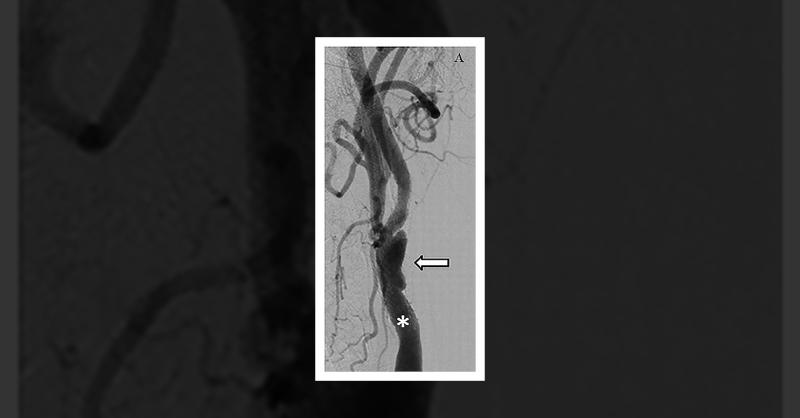

A 72-year-old man with a history of diabetes mellitus, hypertension, and smoking presented with blurred vision and dizziness, reminiscent of previous carotid artery issues. A carotid ultrasound revealed significant stenosis in his left internal carotid artery, while angiography showed eccentric stenosis with an ulcerative crater at the stent site.